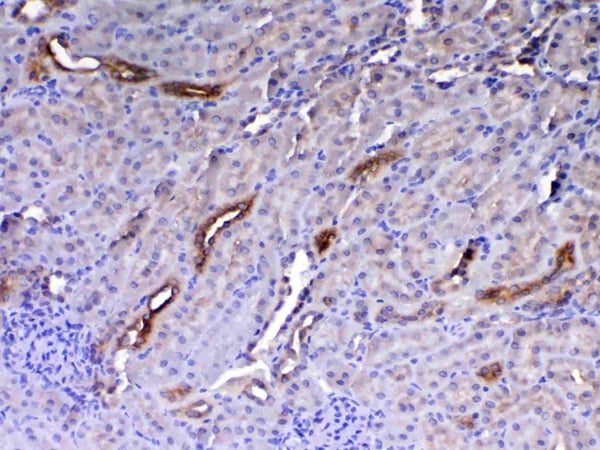

Periostin, Polyclonal Antibody (Cat# AAA19149)

No cross reactivity with other proteins.